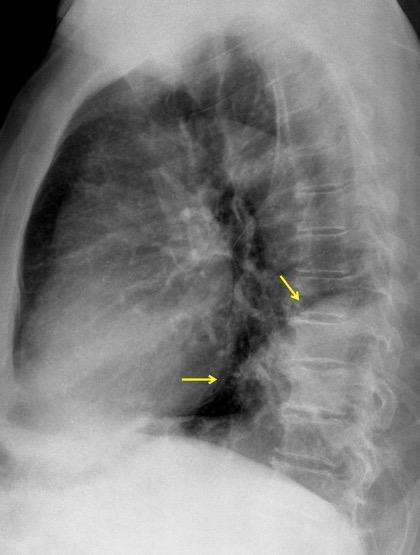

30 años

Borramiento de la banda PARA-aórtica por AdenoCa. de LII, no visible en 2005

Colapso de LII. TC: secreciones bronquiales.

Endoscopia tapón mucopurulento extraído